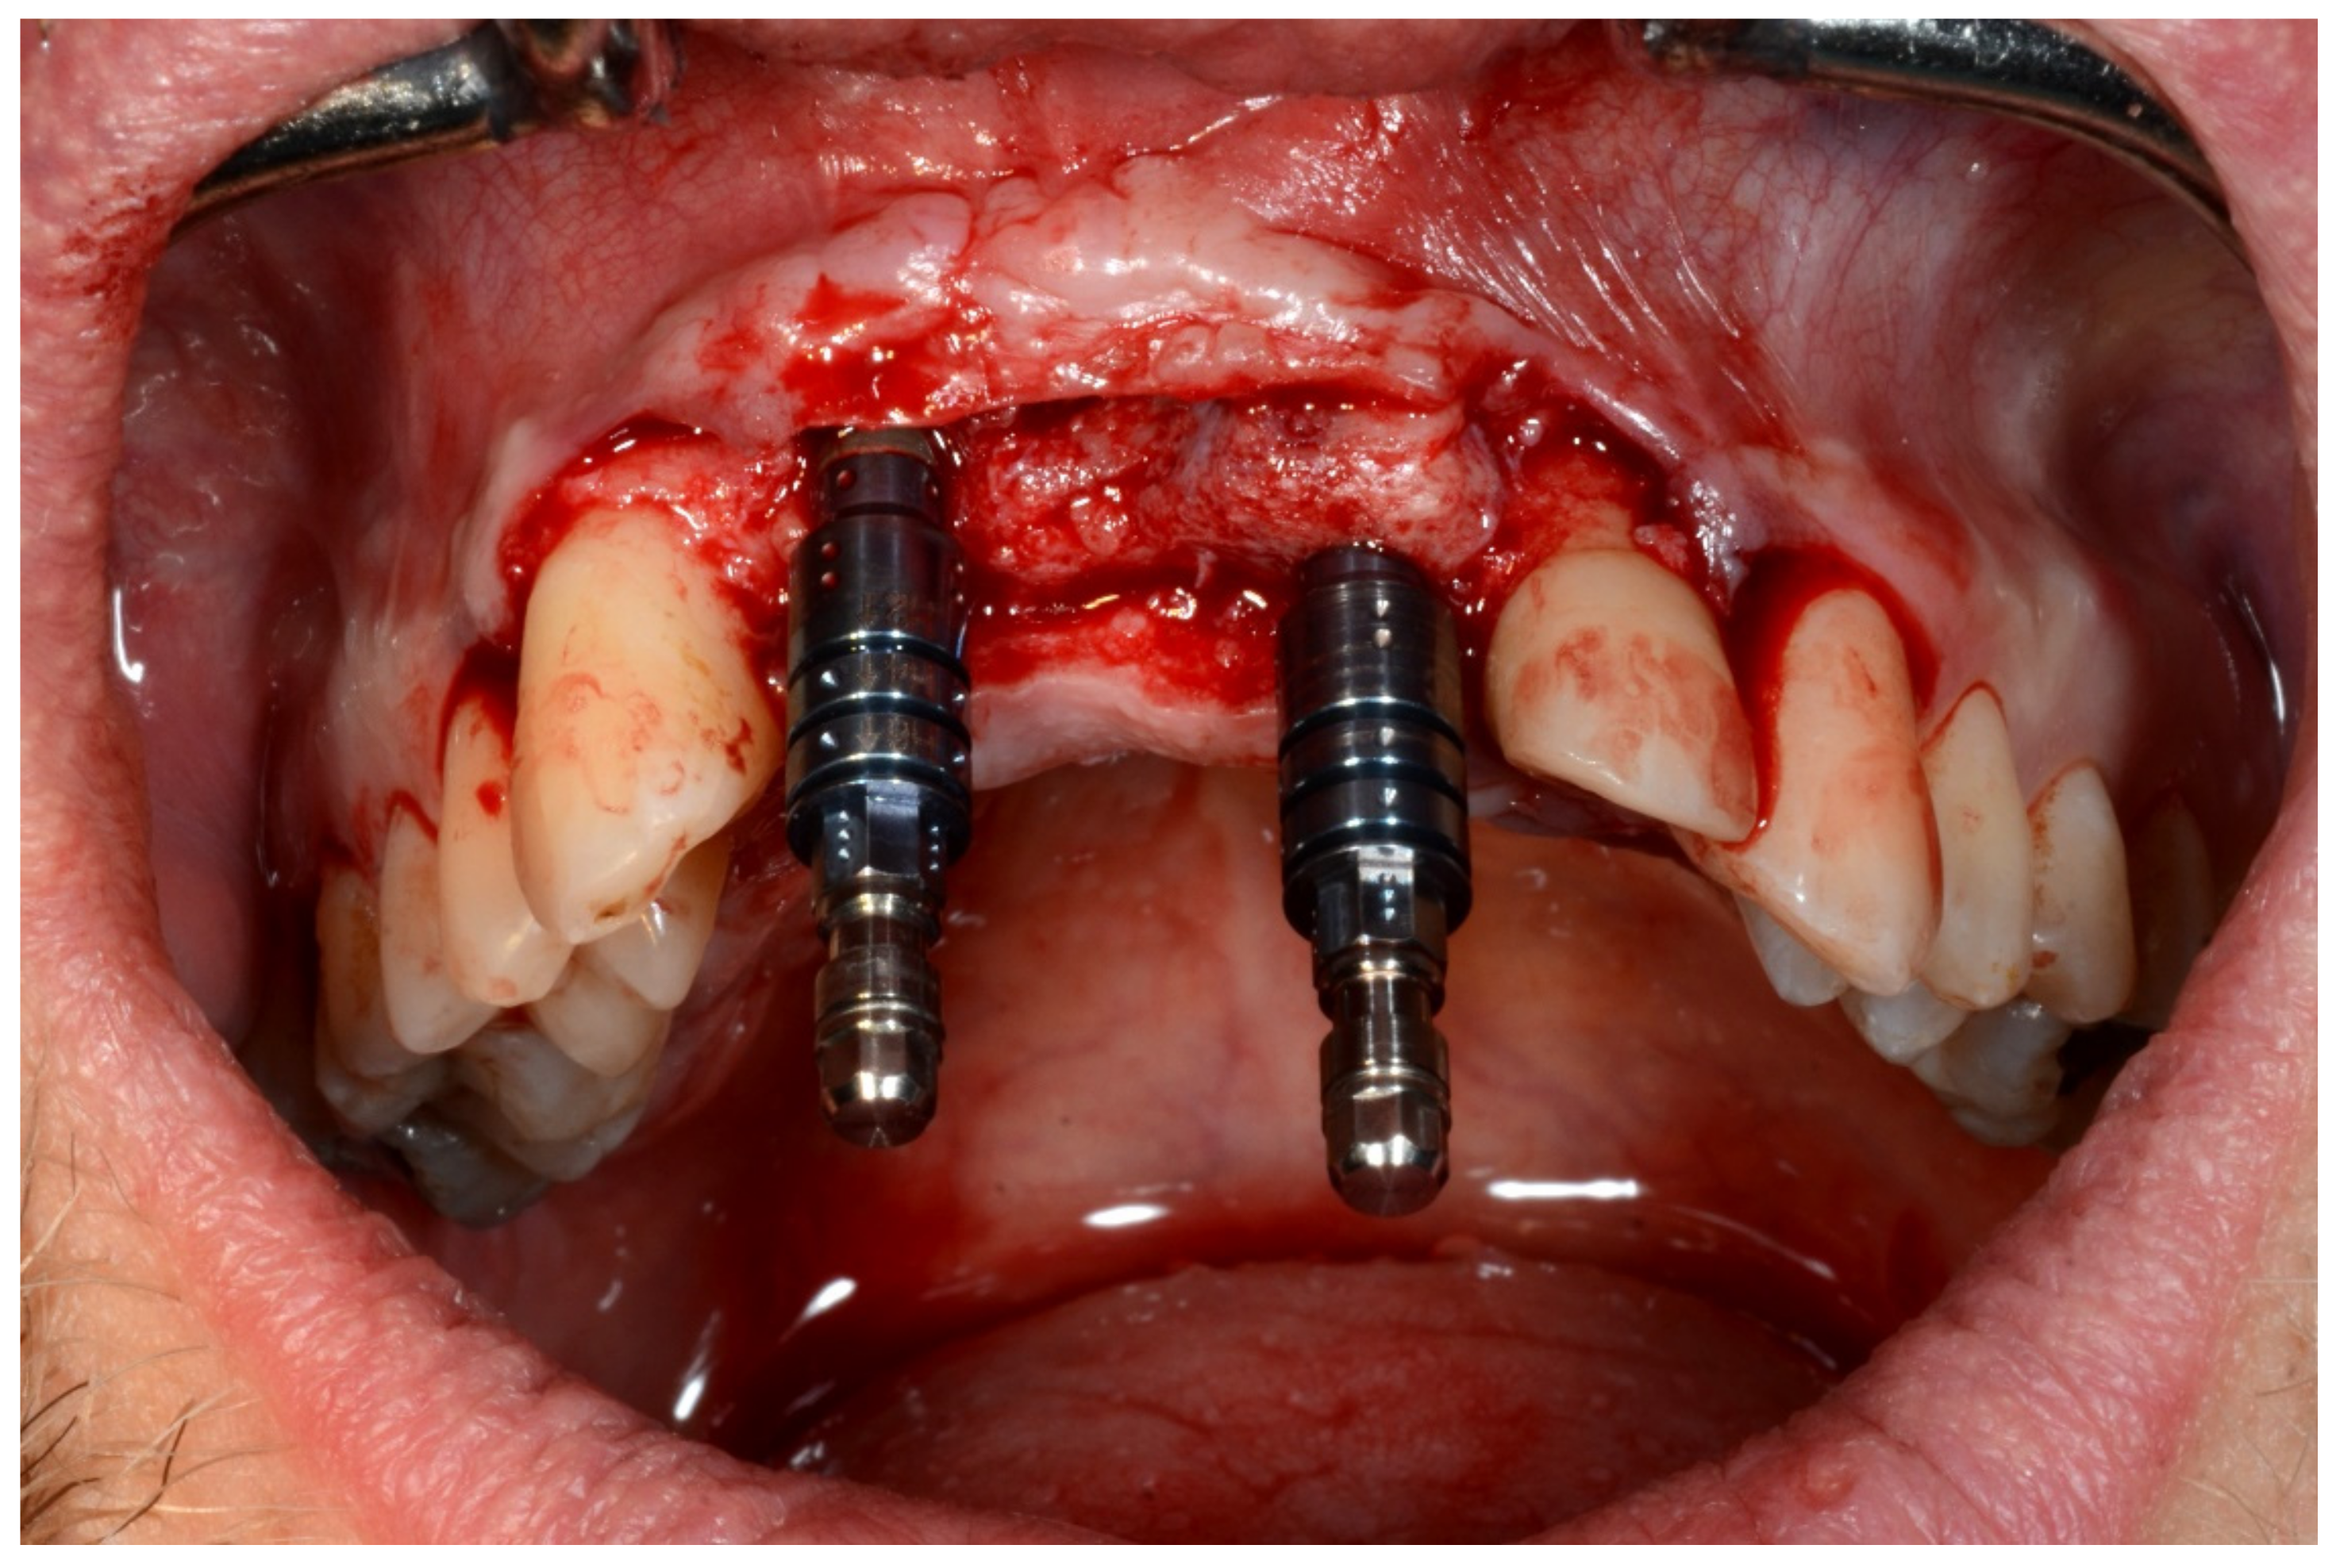

In November 2017, two guided dental implants were placed at sites # 12 and # 21 (Figure 7, Figure 8, Figure 9, Figure 10 and Figure 11).

Figure 9.

Guided implant insertion.

Figure 10.

Frontal verification of the parallel placement of the implants.